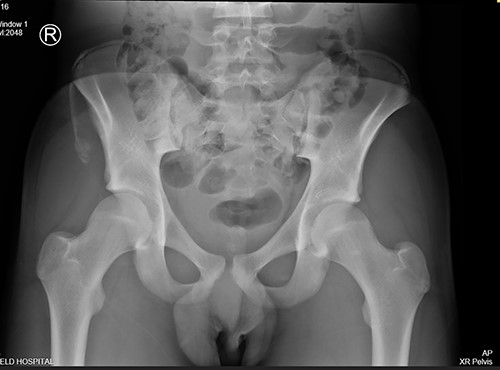

The anterior–posterior plain film X-Ray of pelvis demonstrated an avulsion fracture of the right ASIS and IC apophysis with 1.5 cm displacement (Fig. 1). Lateral view of the hip showed no extension into the joint. There was no radiological evidence of chronic overuse or previous injury. Computed tomography (CT) imaging was performed to better identify the injury; 3D volume reconstruction clearly demonstrated the unique fracture pattern of an ASIS avulsion in addition to an avulsion of the distal iliac apophysis extending ~5 cm with the described displacement (Figs 2–4).

3D reconstruction of tomographic CT scan illustrating avulsion fracture of ASIS and IC apophysis with its latero-inferior displacement (P - Posterior).